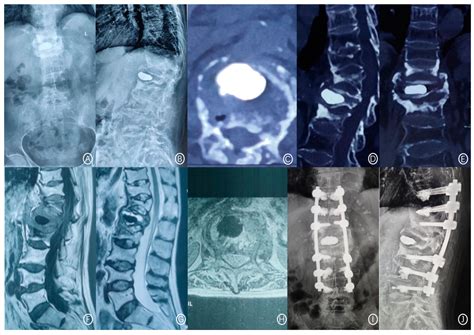

Predictive Factors for Bone Cement Displacement following Percutaneous ...

mdpi.com